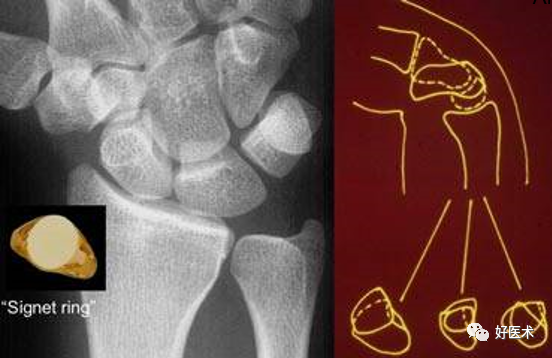

3.腕骨弧線

- 弧線Ⅰ為沿舟骨、月骨、三角骨近側凸面的光滑曲線。

- 弧線Ⅱ為其遠側凹面的光滑曲線。

- 弧線Ⅲ為頭狀骨和鉤骨近側的曲面。

腕骨弧線中斷

弧線中斷提示骨折或韌帶斷裂導致的半脫位或脫位。

上圖顯示弧線 Ⅰ 在月骨-三角骨關節處的中斷。

弧線 Ⅱ 中斷於舟月關節和月骨-三角骨關節(上圖)。弧線 Ⅰ 雖有缺口但仍呈光滑弧線,可認為是完整的。

弧線 Ⅲ 中斷,上圖顯示頭狀骨-鉤骨關節異常階梯狀改變。